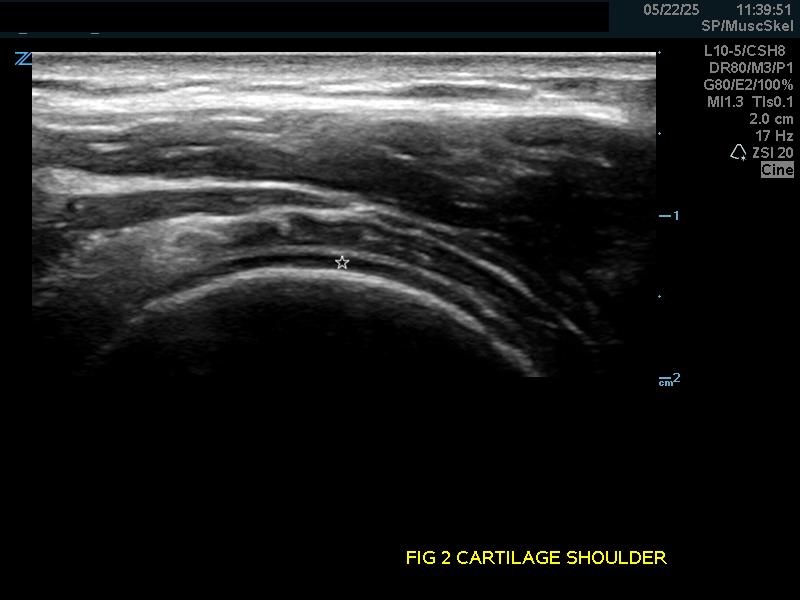

Hyaline Articular Cartilage: Appears as a thin very hypoechoic rim over a hyperechoic bony cortex. It is so hypoechoic it may be confused with fluid.

Figure 2.

(A) Hyaline articular cartilage (star) of the shoulder and (B) knee.